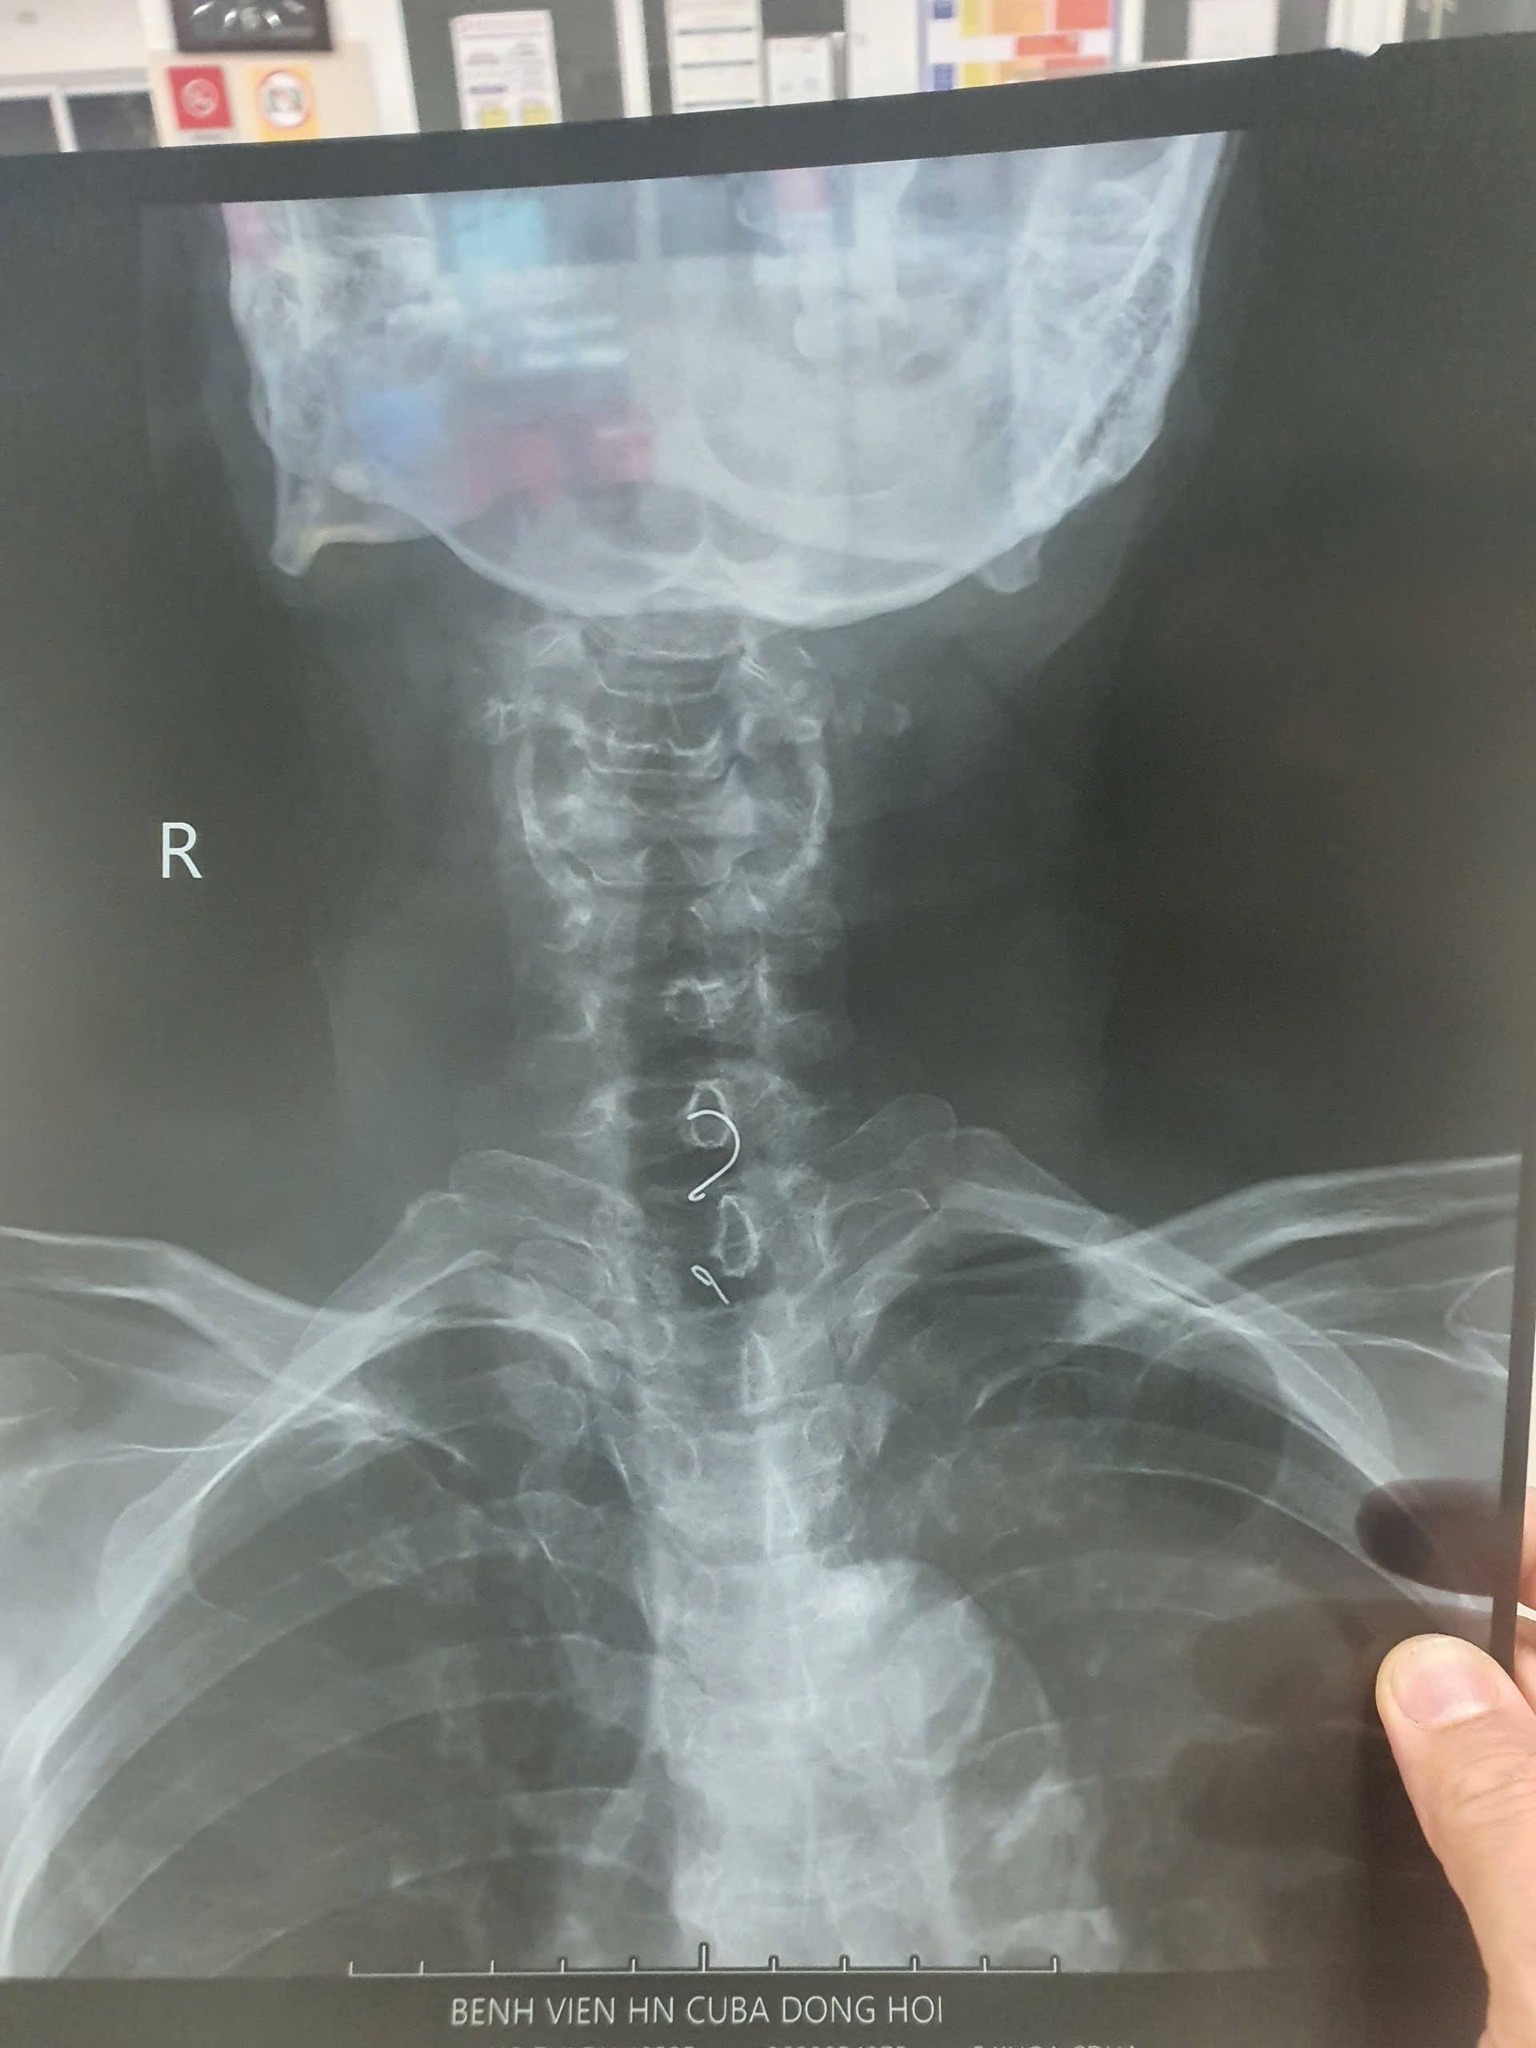

Không chỉ ở trẻ nhỏ, các ca hóc dị vật ở người lớn cũng diễn ra khá phổ biến với nhiều tình huống bất ngờ. Tại khoa Nội tiêu hóa – Huyết học lâm sàng (Bệnh viện hữu nghị Việt Nam – Cu Ba Đồng Hới), thời gian qua liên tục tiếp nhận các ca dị vật thực quản.

Đáng chú ý, ngày 19.1, các bác sĩ tiếp nhận một ca xuất huyết tiêu hóa nôn ra máu, đồng thời nhận thông tin về bệnh nhân đau thắt ngực dữ dội. Qua chẩn đoán hình ảnh, phát hiện dị vật nghi đâm xuyên cơ thực quản. Sau hội chẩn liên khoa và phối hợp giữa các chuyên khoa tim mạch, ngoại tổng hợp, ê kíp đã nội soi gắp thành công một chiếc xương cá dài gần 7 cm, đảm bảo an toàn cho người bệnh.

Thầy thuốc ưu tú, bác sĩ chuyên khoa 2 Nguyễn Duy Thạch, Trưởng khoa Nội tiêu hóa – Huyết học lâm sàng (Bệnh viện hữu nghị Việt Nam – Cu Ba Đồng Hới), cho biết thực quản có 5 đoạn hẹp sinh lý, dễ khiến dị vật mắc kẹt. Thống kê cho thấy dị vật thường dừng lại ở vùng cổ (74%), đoạn ngực (22%) và đoạn dưới ngực (4%).